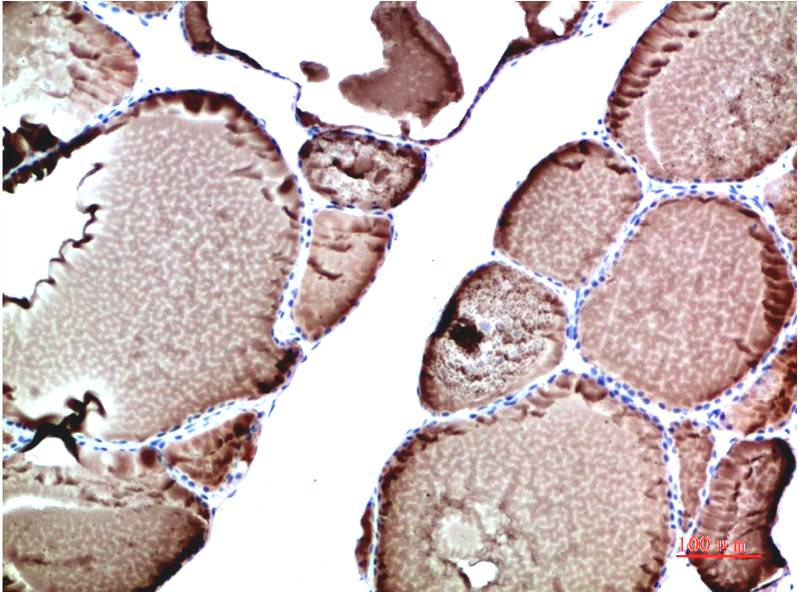

TTR Mouse Monoclonal Antibody(5G9)

Applications :WB, IHC

| Recommended dilutions: | WB 1:1,000-2,000 IHC 1:100-200 |

| Specificity: | The TTR Mouse Monoclonal Antibody can detects endogenous TTR proteins. |